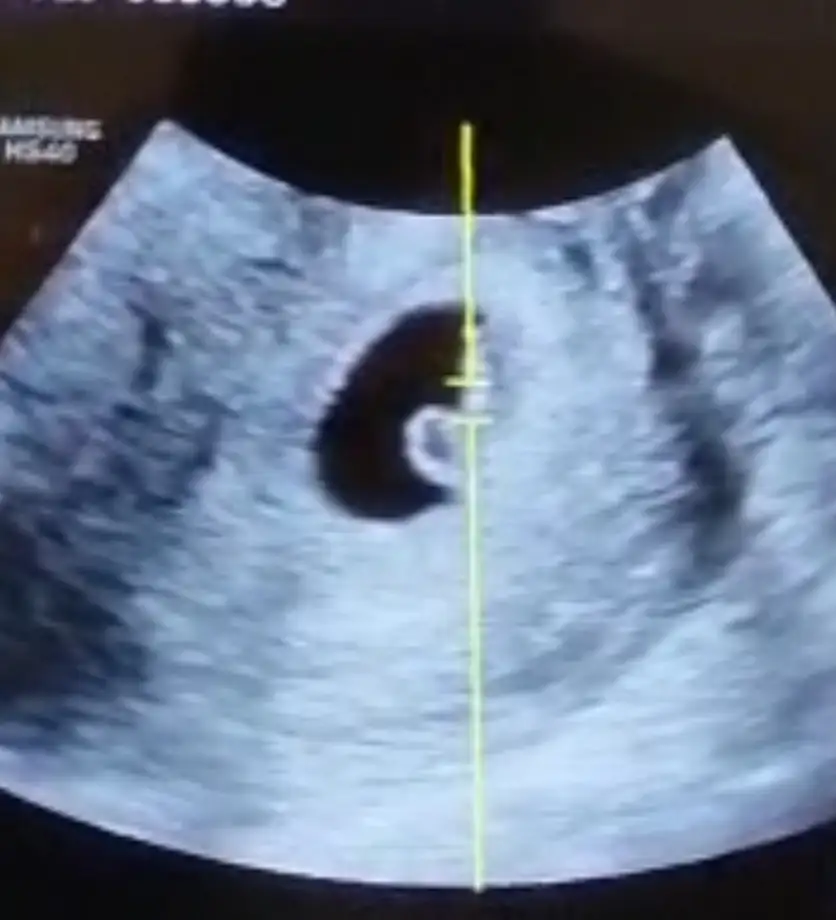

Ya ne kadar doğru ne kadar yanlış bilmem ama oğlumda sabah ilk idrar şu içmeden tabi rengi açıksa gogus uçların koyulasmaya başladıysa ve bebek usg de doktor bakınca göbek deliginin altındaysa erkek oluyor genelde bide erkek çocuğu balık gibidir sürekli küçük dahi olsa usg de hareket halindedir en azından ben böyleydim yengelerim de böyle belirtileri vardıKese yuvarlaksa ne oluyor pekiEki Görüntüle 3255223

Kesenin sekline gore yorum yapiyorlar ya ondan :)Ya ne kadar doğru ne kadar yanlış bilmem ama oğlumda sabah ilk idrar şu içmeden tabi rengi açıksa gogus uçların koyulasmaya başladıysa ve bebek usg de doktor bakınca göbek deliginin altındaysa erkek oluyor genelde bide erkek çocuğu balık gibidir sürekli küçük dahi olsa usg de hareket halindedir en azından ben böyleydim yengelerim de böyle belirtileri vardı

Ay ilk çocuk sağlıklı olsunda farketmez benim içinBen de erkek diyorum canım kese şeklinden dolayı, öyle çok bir şey bildiğimden değil de benim oğlanın kesesi de böyle fasülyemsiydi oradan çıkarım yaptım. Sen ne hissediyorsun ve ne istiyorsun

Fasulye benzeri bir kese ile yuvarlak kese arasında cinsiyetler mi değişir bilemedim şimdi ama o da bir yaklaşım tabi ki sağlıklı olsunlar daha cinsiyetlere kadar epey vakit var keseden tahminler yanıltıcı olabilir diye düşünüyorum sonuçta daha kaç gramlar kiiBen de erkek diyorum canım kese şeklinden dolayı, öyle çok bir şey bildiğimden değil de benim oğlanın kesesi de böyle fasülyemsiydi oradan çıkarım yaptım. Sen ne hissediyorsun ve ne istiyorsun